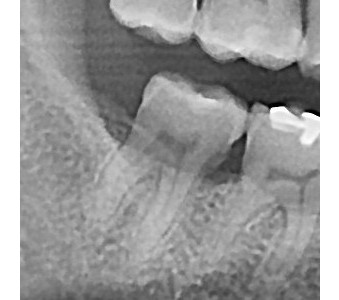

결과로 증명합니다.

국제모아치과의

실제 임상 증례